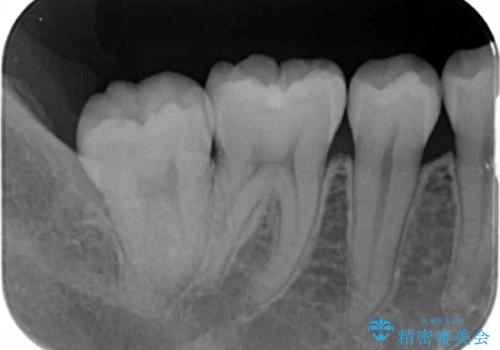

- 奥歯の溝の黒ずみが気になるとのことで来院されました。

変色しない材料をご希望されたためセラミックインレーでの治療となりました。

- 右下7 セラミックインレー 77,000円費用は治療当時の料金となります